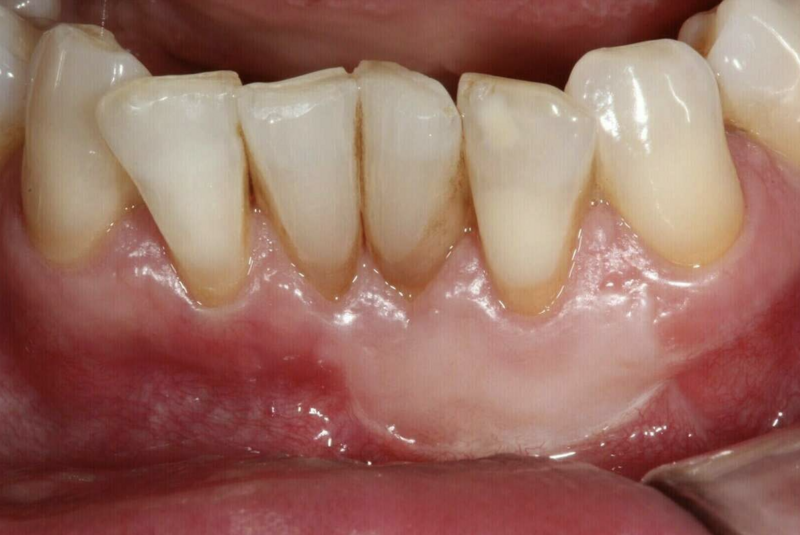

Dans le cas où on est en présence d'une récession gingivale et que celle-ci continue de progresser soit par la maladie parodontale soit par un brossage traumatique ou que le sensibilité thermique est importante et gênante, on peut greffer de la gencive et maintenir un environnement propice à l'hygiène.

Après